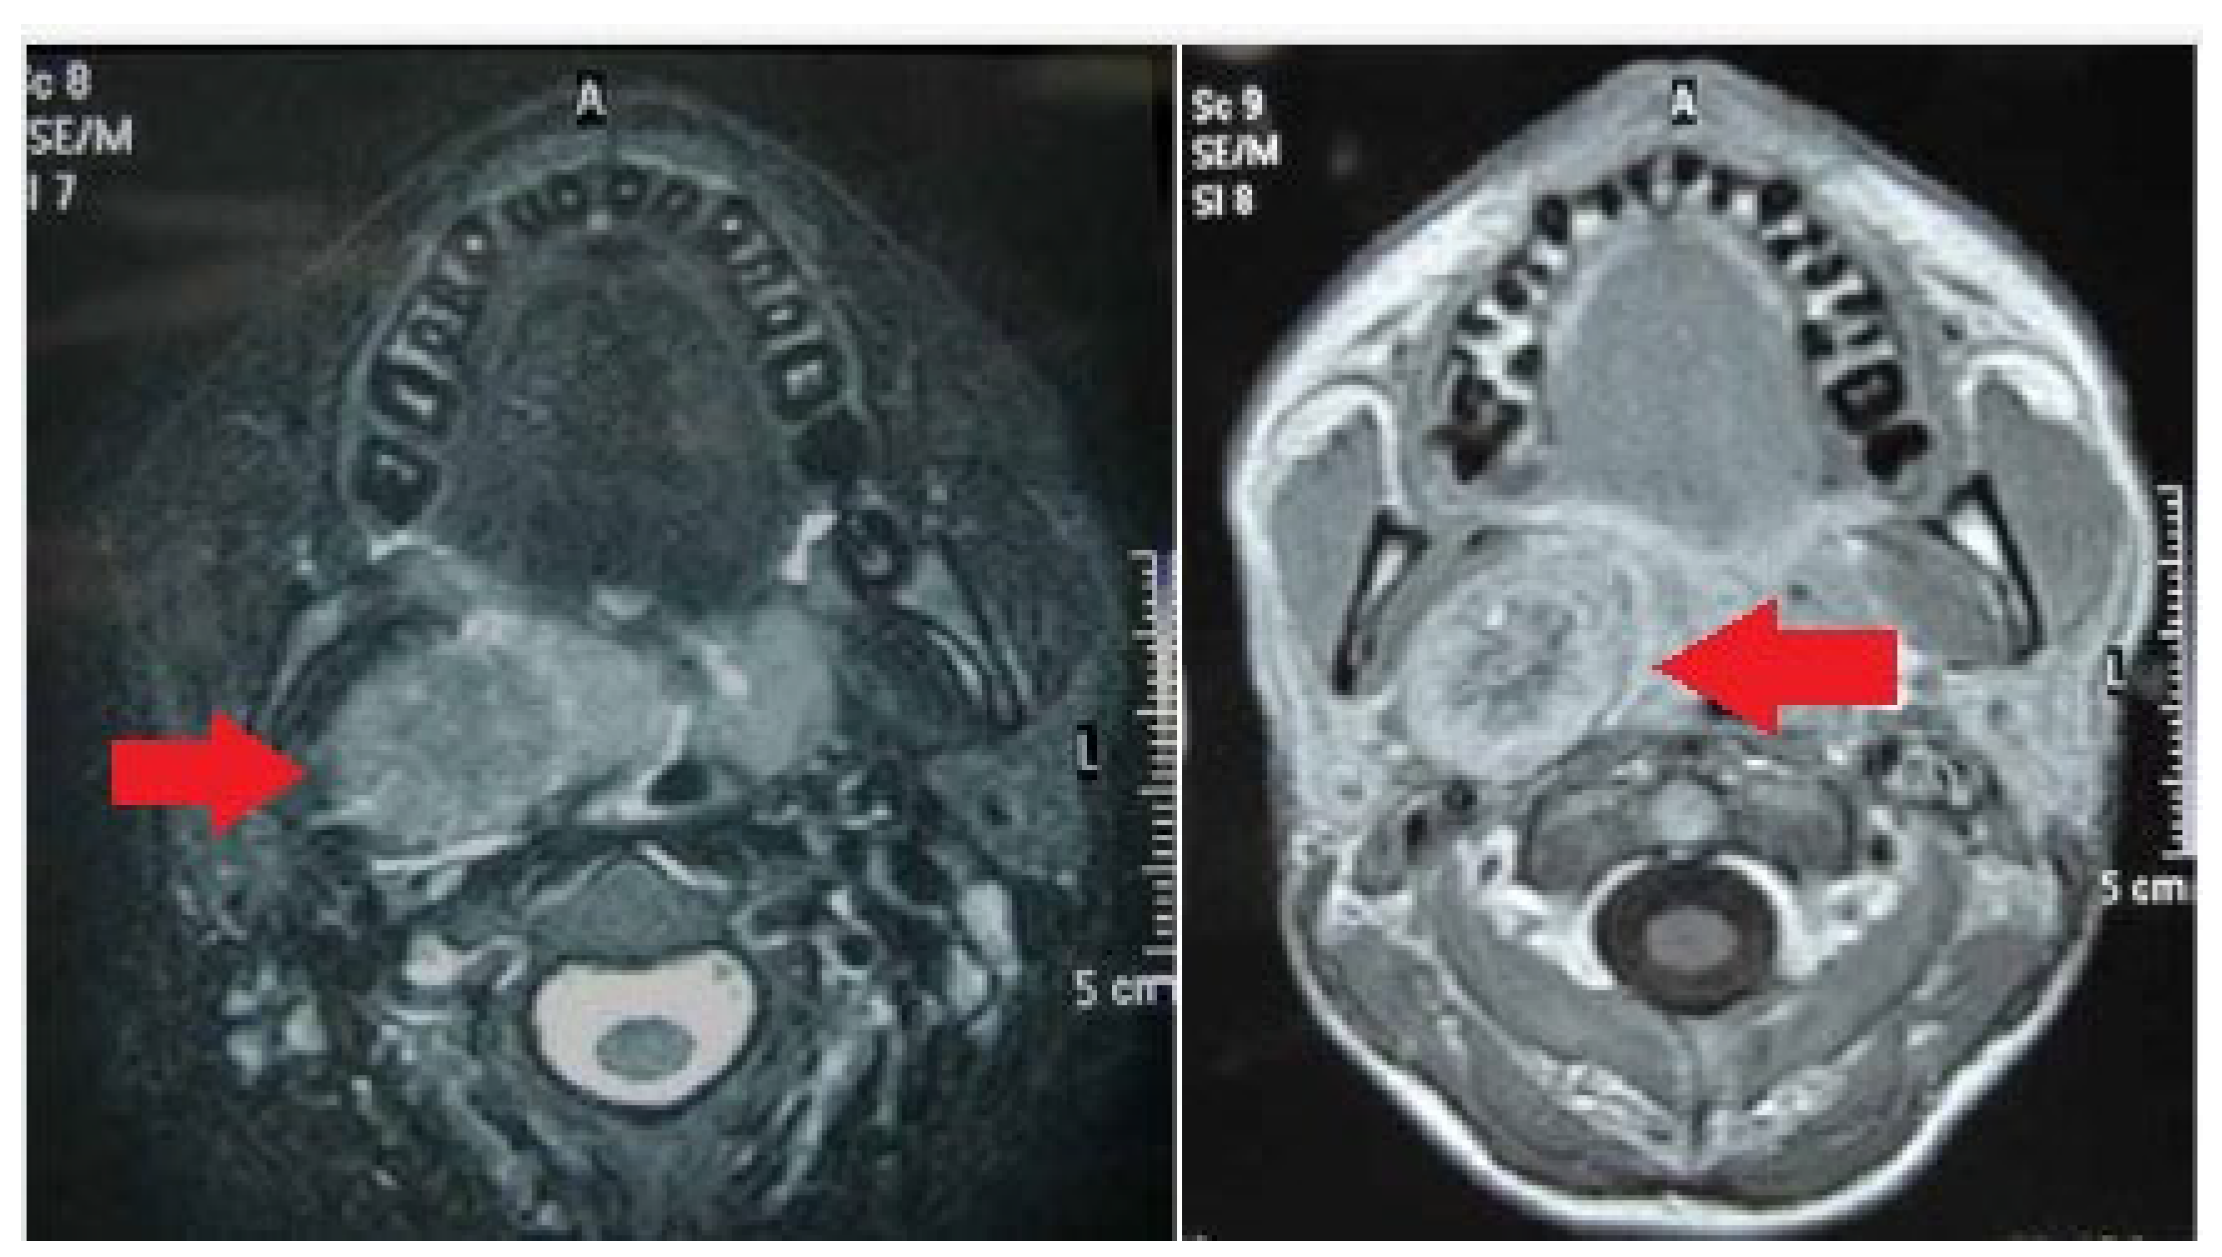

- Crist, J.; Hodge, J.R.; Frick, M.; Leung, F.P.; Hsu, E.; Gi, M.T.; Venkatesh, S.K. Magnetic Resonance Imaging Appearance of Schwannomas from Head to Toe: A Pictorial Review. J. Clin. Imaging Sci. 2017, 7, 38. [Google Scholar] [CrossRef]

- Anil, G.; Tan, T.Y. CT and MRI evaluation of nerve sheath tumors of the cervical vagus nerve. Am. J. Roentgenol. 2011, 197, 195–201. [Google Scholar] [CrossRef]

- Lin, J.; Martel, W. Cross-sectional imaging of peripheral nerve sheath tumors: Characteristic signs on CT, MR imaging, and sonography. Am. J. Roentgenol. 2001, 176, 75–82. [Google Scholar] [CrossRef]